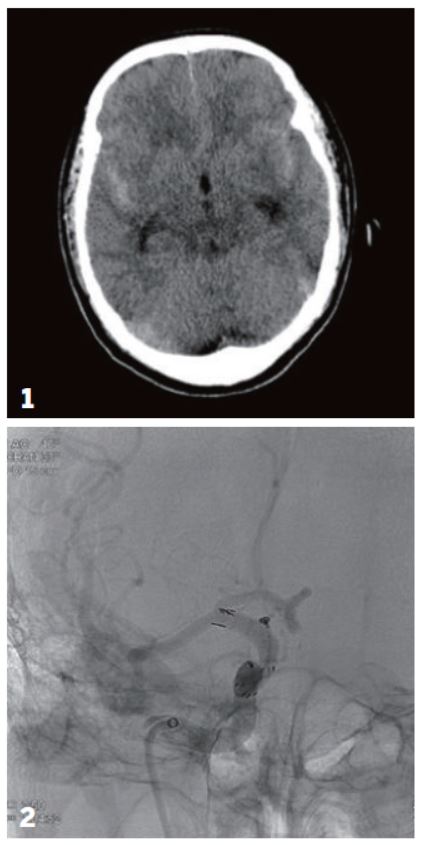

▲1 회색 뇌실질을 따라 하얗게 보이는 것이 뇌지주막하 출혈로 최초 내원시 촬영된 뇌 CT 사진.

2 미세 카테터를 이용해 코일을 박리성 뇌동맥류에 삽입하여 치료하는 장면

“환자가 처음 병원에 왔을 때는 약간의 출혈이 있었지만 더 이상은 없었어요. 뇌혈관조영술을 통해 찢어진 부위가 의심되는 부위가 있었지만 뚜렷하지 않아, 일단 환자의 혈압을 안정시키고 나서 이틀 후인 6월 8일에 뇌혈관조영술을 다시 시도했어요. 혈관 모양이 변화된 것이 확인돼 뇌동 맥박리에 의한 뇌지주막하출혈이라고 확진하고 스텐트 삽입술을 진행했습니다. 더이상 출혈이 생겨서는 안 되니까요.”

혈관에 튀어나온 부위는 높이가 1.45mm, 너비가 2.9mm로 여드름 크기에 불과했다. 1m 밖에서 얇은 실을 여드름 안에 넣어야 했다. 게다가 터지면 환자의 생명이 위험해질 수도 있었다. 시술은 6월 22일에 이뤄졌다.